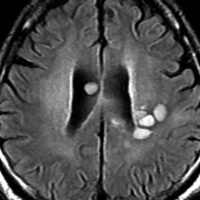

MRI画像所見 60代で嚥下障害と構音障害で発症した例

延髄から中脳まで腫瘍があって脳幹部が腫れています。この画像ですと,小児のびまん性橋膠腫(DIPG,びまん性正中グリオーマ)のように見えます

両側視床から大脳基底核,両側大脳半球深部白質,脳梁まで広範囲に腫瘍が存在します。退形成性星細胞腫のようにまだらにガドリニウム増強されます。